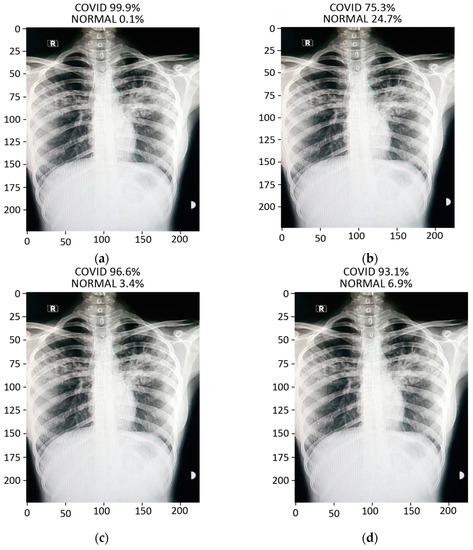

The prediction result for a chest X-ray of a local COVID-19-positive patient for each model is given in Figure 13a–d. The DenseNet-121 had the highest probability percentage of COVID-19, i.e., 99.9%. In order to highlight the area where the model is paying the most attention during feature extraction, the Grad-CAM technique was applied. The Grad-CAM results of all four models under study are given in Figure 14. Moreover, the results of the predicted normal patients for each model are shown in Figure 15a–d. Considering these results, the MobileNet has the highest probability of 96.8% for the prediction of a normal chest X-ray.

Figure 13.

Results of prediction on a verified local Pakistani COVID-19 chest X-ray: (a) DenseNet-121; (b) VGG16; (c) MobileNet; (d) ResNet-50.